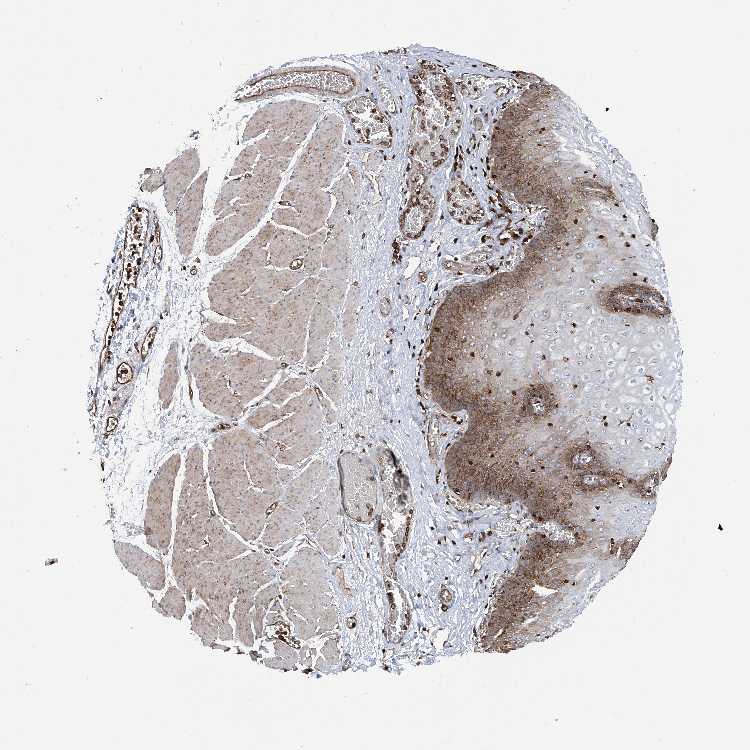

ESOPHAGUS - Antibody stainingi

Antibody staining in the annotated cell types in the current human tissue is reported as not detected, low, medium, or high, based on conventional immunohistochemistry profiling in selected tissues. This score is based on the combination of the staining intensity and fraction of stained cells.

Each image is clickable and will lead to virtual microscopy that enables deeper exploration of all samples and also displays staining intensity scores, fraction scores and subcellular localization as well as patient and tissue information for each sample.

Antibody HPA028973

Squamous epithelial cells Medium